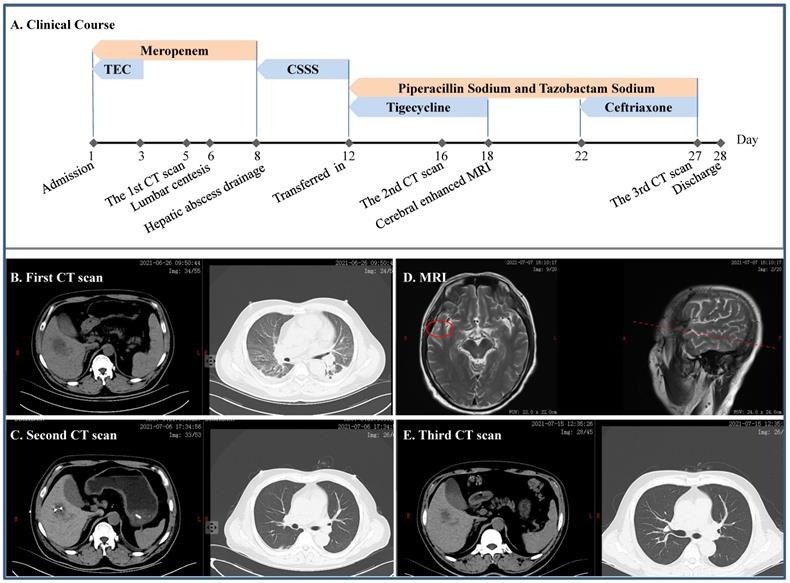

Severe infection caused by the cKp

A 49-year-old man without self-reported diabetes was admitted to the intensive care unit (ICU) due to fever of 39.0 ºC for 2 days, accompanied by headache, disorder of consciousness and seizure (Figure 1). He was found then to have liver abscess, pulmonary infection, septic shock, multiple organs failure including respiratory failure and acute kidney injury (AKI), digestive tract bleeding, impaired coagulation and, actually, diabetes. Meropenem and tigecycline were initially given, which were replaced by cefoperazone sodium and sulbactam sodium. Mechanical ventilation and continuous renal replacement therapy (CRRT) were employed ad interim, lumbar centesis and hepatic abscess drainage performed, whereas cerebrospinal fluid yielded no positive finding but metagenomics next generation sequencing (mNGS) identified cKp from his blood. Once transferred to our department, we gave him piperacillin sodium and tazobactam sodium in combination with tigecycline, which was switched to ceftriaxone after a headache-driven contrast-enhanced cerebral MRI found lesion to his right temporal lobe. Free of headache and detached from hemodialysis, the patient eventually had full recovery.

Figure 1

Clinical course and imaging findings in the patient with cKp infection. A: Major therapeutic procedures during the patient's hospital stay. B: The first CT scan after admission showing pulmonary infection and hepatic abscess. C: The second CT scan after the patient was transferred in showing gross normal pulmonary field and drained hepatic abscess. D: Contrast-enhanced MRI showing lesion on the right temporal lobe. E: CT scan prior to discharge. TEC and CSSS: teicoplanin and cefoperazone sodium and sulbactam sodium, respectively.